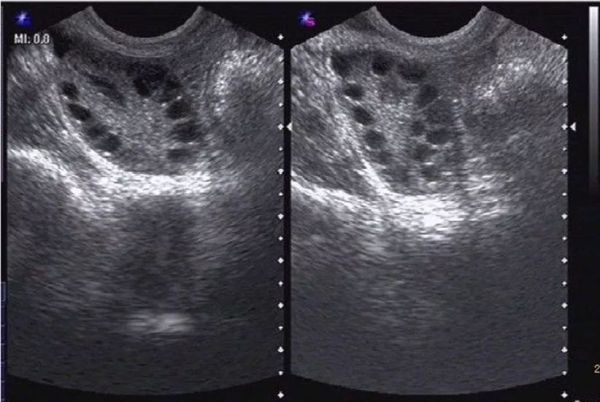

这样的事情在门诊的女性患者中很常见,有些到医院一检查,发现自己是“多囊卵巢综合征”!

“多囊卵巢综合征”是女性常见的一种内分泌疾病,现代医学认为这个病是卵巢没有排卵、体内的雄激素升高等等。

同时卵巢也得不到冲脉血的滋养,卵泡发育不好,甚至无法正常排卵。

具体到女性,子宫及卵巢的气血会出现瘀滞,卵巢气血不通后,卵泡不能正常排出来,被堵在卵巢内,时间久了,也会导致多囊卵巢,甚至宫外孕。